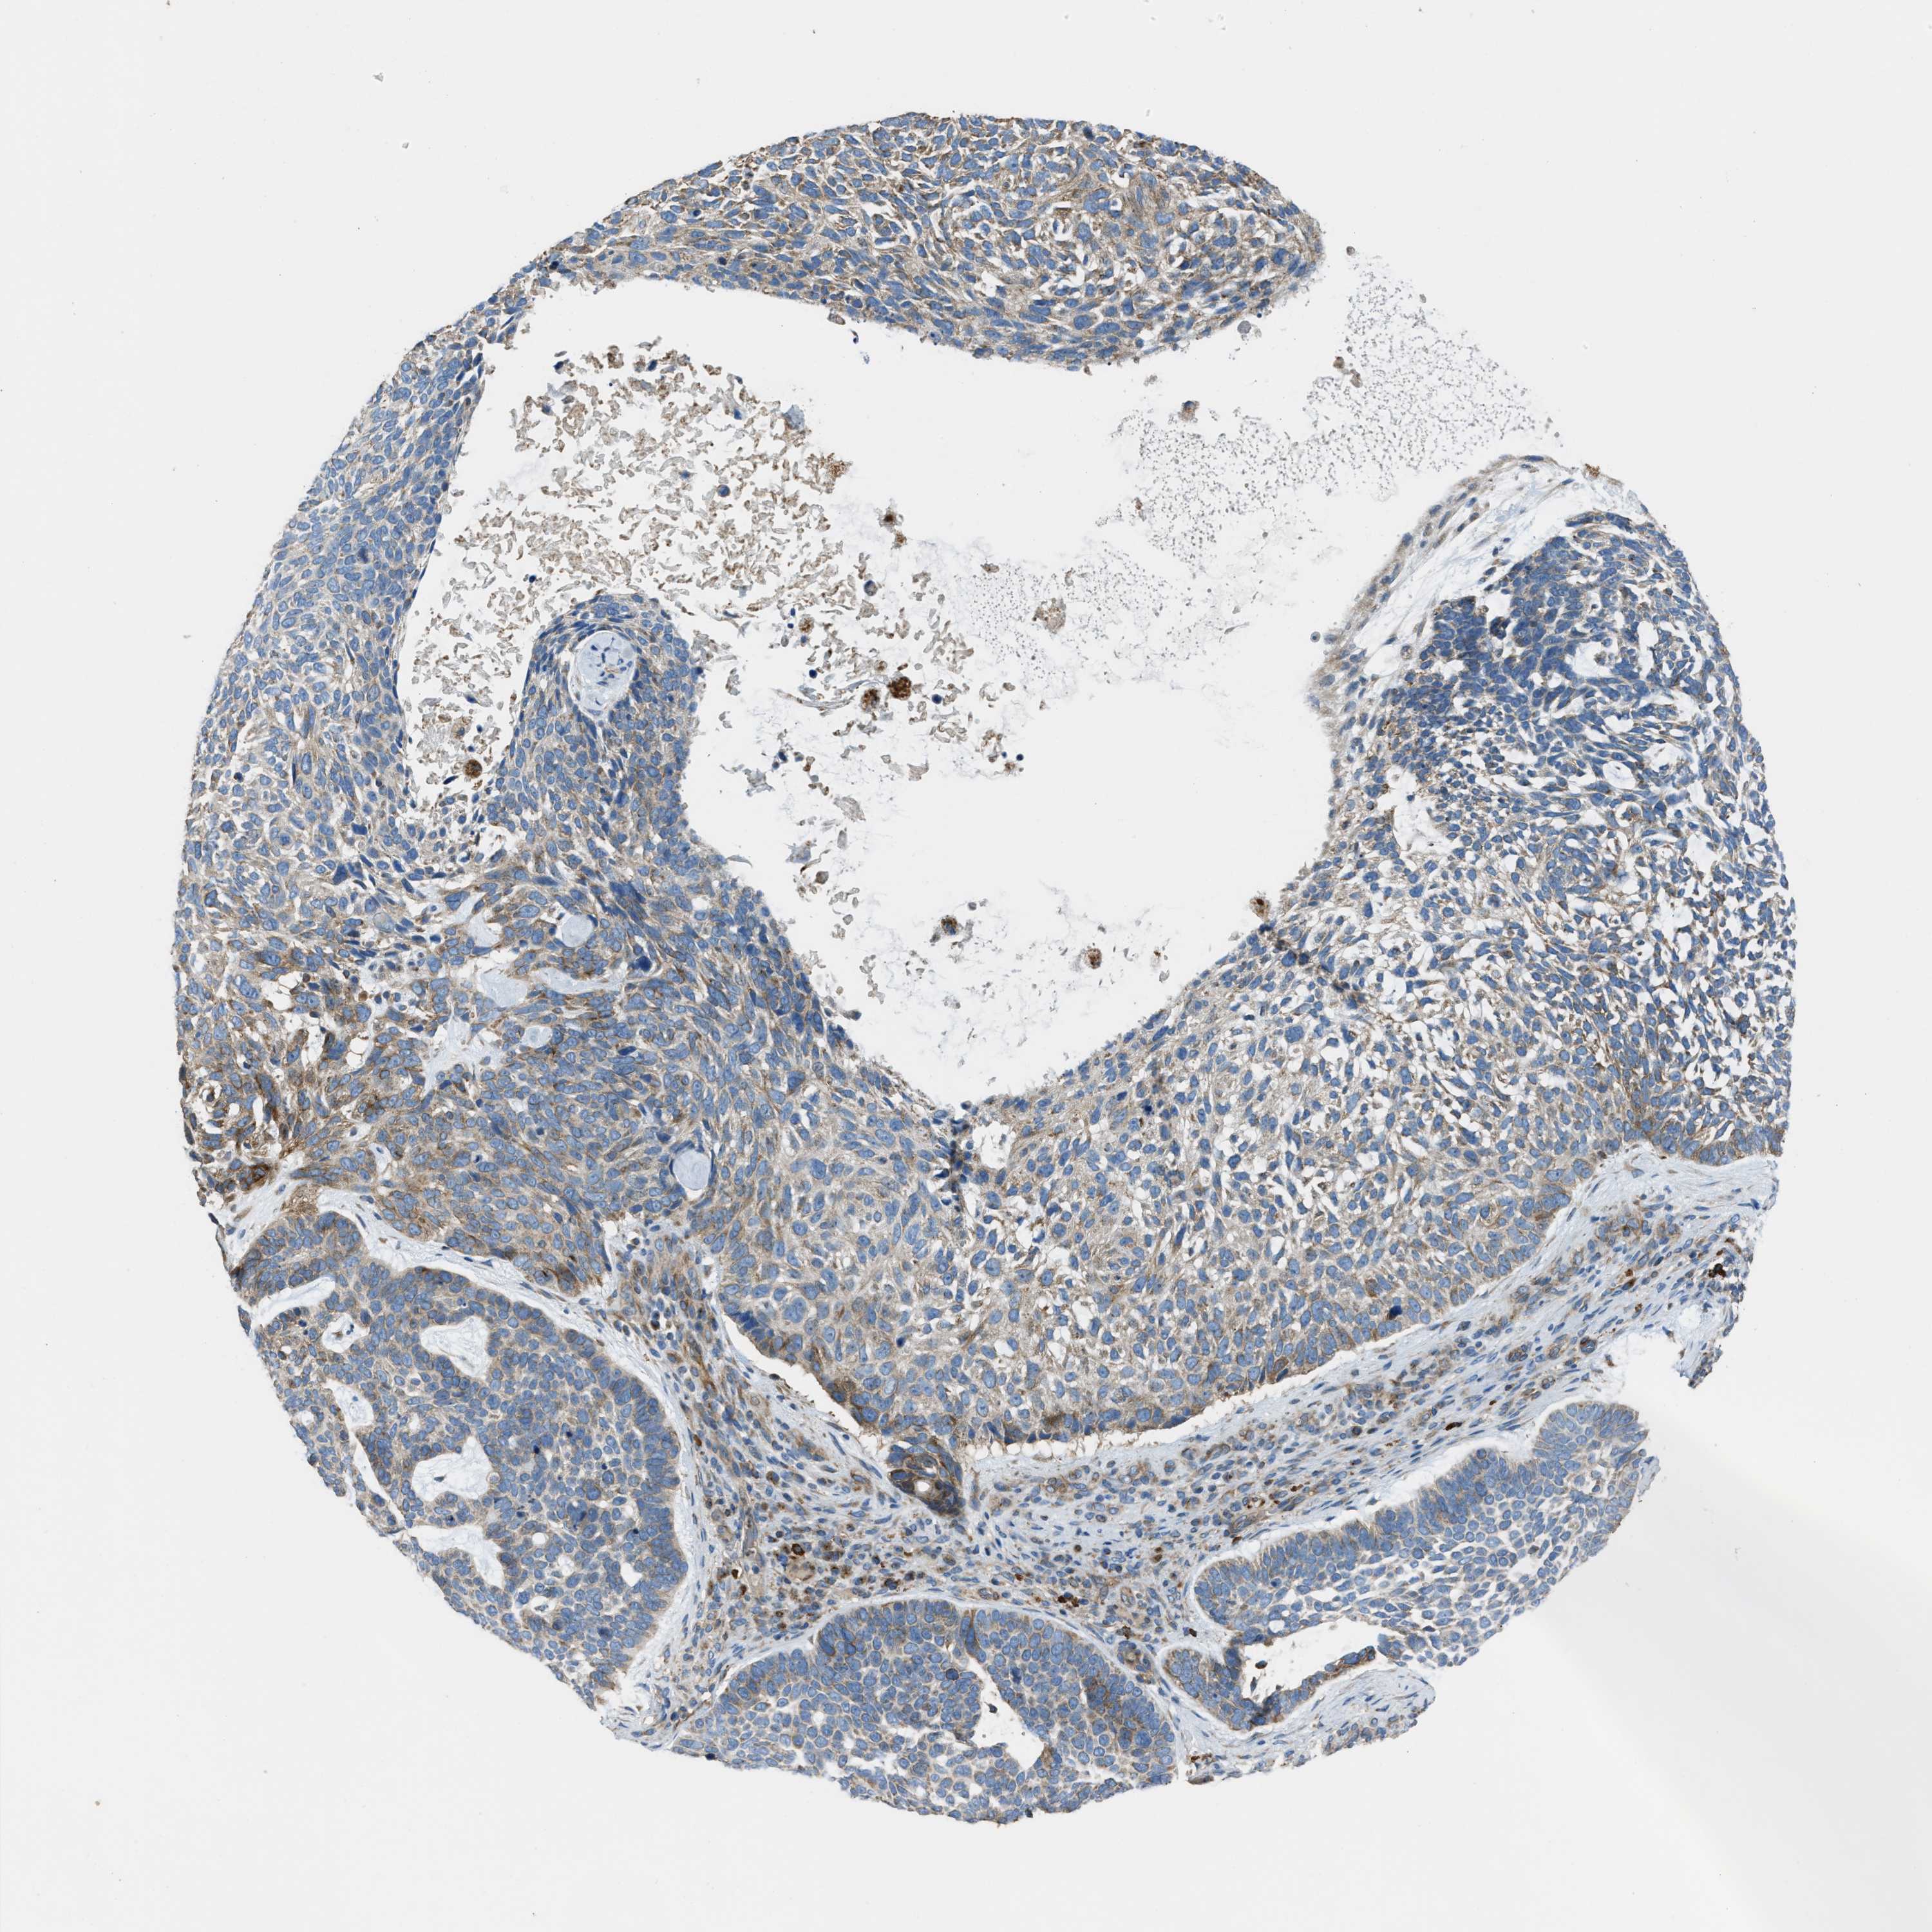

Basal cell and squamous cell cancer

SKIN CANCER - Protein expressioni

A mouse-over function shows sample information and annotation data. Click on an image to view it in a full screen mode. Samples can be filtered based on level of antibody staining by selecting one or several of the following categories: high, medium, low and not detected. The assay and annotation is described here.

Antibody stainingi

Antibody staining in the annotated cell types in the current human tissue is reported as not detected, low, medium, or high, based on conventional immunohistochemistry profiling in selected tissues. This score is based on the combination of the staining intensity and fraction of stained cells.

Each image is clickable and will lead to virtual microscopy that enables deeper exploration of all samples and also displays staining intensity scores, fraction scores and subcellular localization as well as patient and tissue information for each sample.

Antibody HPA021167

Staining

High

Medium

Low

Not detected

Intensity

Strong

Moderate

Weak

Negative

Quantity

>75%

75%-25%

<25%

None

Location

Nuclear

Cytoplasmic/membranous

Cytoplasmic/membranous,nuclear

Basal cell carcinoma